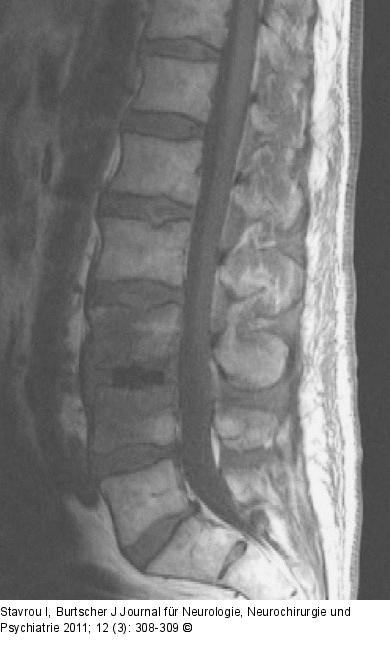

Abbildung 2: Wirbelkörper - MRT 1,5 Tesla, sagittale T1-gewichtete Sequenz nach Kontrastmittelgabe: Zustand nach X-LIF (am 5. postoperativen Tag) mit perkutaner transpedikulärer Stabilisierung bei L3/L4. Keine Kontrastmittelaufnahme der Wirbelkörper L3/L4 nachweisbar. |

Abbildung 2: Wirbelkörper - MRT